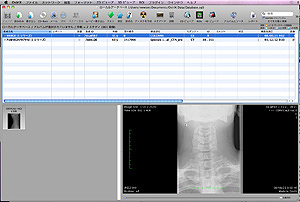

OsiriX(オザイリクス)という医用画像ビューワを日本で公式サポートしております。

OsiriX(オザイリクス)は、医用画像ビューワの表示とその画像からの分析す

るために開発された高性能なDICOMビューワです。また同時に DICOM通信

機能も備えた簡易的PACS としても利用可能な Mac OSX 専用アプリケー

ションです。無料でだれでもダウンロードできます。